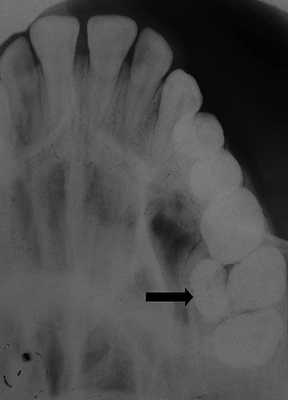

Сверхкомплектный зуб определен как парамоляр. Коронка парамоляра имела два бугорка и весьма сильно напоминала строение постоянного премоляра. Зуб повернут по оси, с расположением щечной поверхности дистально и мезиальной поверхности щечно. На мезиальной стороне парамоляра обнаружено кариозное поражение (Фото 2). Осмотр мягких тканей выявил воспаление пародонта между первым и вторым молярами и парамоляром. Сделаны рентгеновские снимки: панорамный, прицельный и окклюзионный. Чтение панорамного снимка было затруднено из-за небного расположения зуба. На прицельном и окклюзионных снимках обнаружено, что сверхкомплектный зуб поражен кариесом и имеет один корень (Фото 3 и 4).

Фото 3: Прицельный рентгеновский снимок, показывающий парамоляр с полностью сформованным зубом (указан стрелкой).

Фото 4: Окклюзионная рентгенограмма верхней челюсти, показывающая сверхкомплектный зуб (стрелка).